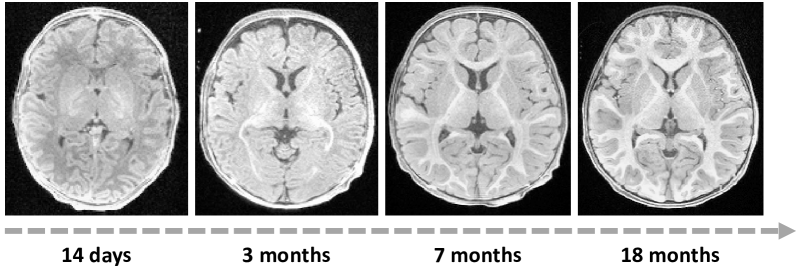

Image generation. Given that CLIP can bridge the gap between image and language, it is also intuitive to apply this technique to text-guided image generation. In this context, Wang et al. [264] make the first attempt to generate customized MRI sequences from routinely acquired scans based on text prompts. Their proposed method, Text-guided Universal MR Image Synthesis (TUMSyn), enables the generation of MRI sequences tailored to specific text-based instructions. These prompts include subject information such as age and gender, along with MRI parameters like scanning field strength, scanner type, voxel size, inversion time, etc. Their pre-trained CLIP text encoder is responsible for converting these text prompts into feature embeddings that can be interpreted by the LIFF model [42], achieving superior generation performance across several evaluation datasets. Likewise, Chung et al. [50] address a specific inverse problem, compressed sensing MRI. They suggest that conditioning diffusion models on such metadata could significantly enhance the performance of this application.